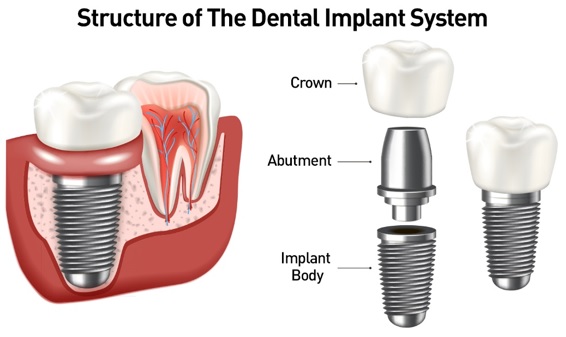

We offer a wide range of dental treatments tailored to your unique clinical and cosmetic needs.